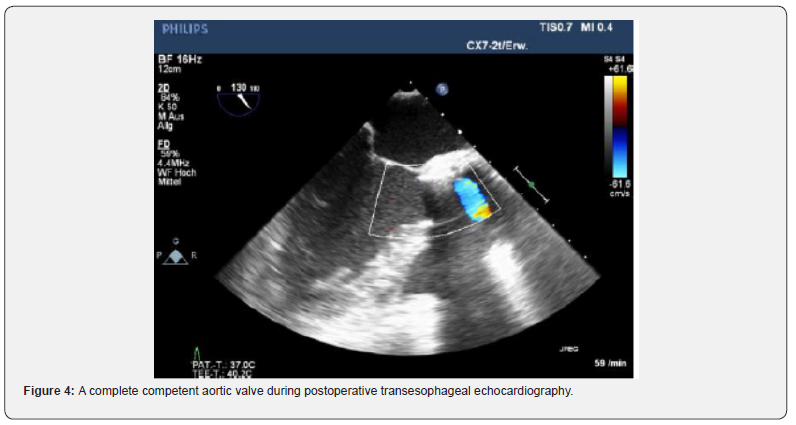

A 59-year-old female patient suffering from recurrent chest pain after acute Stanford Type A aortic dissection (TAAD) presented at our outpatient clinic. Four months prior to this consultation, the patient underwent emergency surgery with aortic root remodeling and replacement of the ascending aorta in deep-hypothermic arrest at another centre. The postoperative period was complicated by pulmonary insufficiency with prolonged ventilation. At the present visit in our department, a control contrast-enhanced computed tomography was performed showing a rest dissection starting at the distal ascending aorta was seen (Figure 1). Additionally a moderate aortic valve regurgitation was seen at transesophageal echocardiography (Figure 2). The patient was urgent taken to the operating theatre for complete open repair. Cardiopulmonary bypass was initiated by re-cannulation of the right axillary artery and the right femoral vein. Hypothermic circulatory arrest at 17.7°C was instituted for implantation of a frozen elephant trunk (E-vita OPEN PLUS Hybrid Stentgraft System 24mm with a stentgraft length of 130mm; Jotec GmbH, Hechingen, Germany), arch replacement and replacement of the aortic valve using a rapid-deployment valve system (23mm) after removing the native aortic valve leaflets. Antegrade brain perfusion was performed for 42 minutes and cross-clamp time was 93 minutes. The postoperative course was uneventful and respirator weaning was achieved within 5 hours. On postoperative day 2, the patient was transferred to the general ward. The patient was discharged home on postoperative day 14 showing excellent aortic valve function, without regurgitation and optimal aortic repair (Figure 3,4). On 6 months follow-up these data could be confirmed (Figure 5).